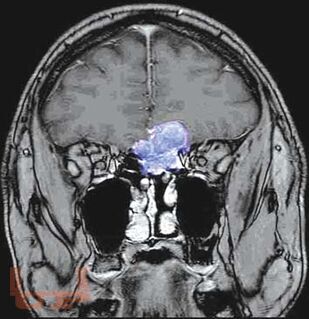

Кратко изложены этиология, особенности эпидемиологии, патогенеза, классификация и основные клинические проявления первичных опухолей головного мозга, современные принципы клиники, диагностики и оказания госпитальной помощи больным с данной патологией. Представлены алгоритмы обследования и лечения больных с наиболее часто встречающимися опухолями в зависимости от стадии течения патологического процесса.